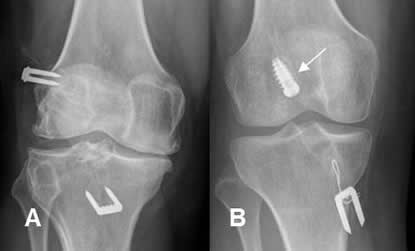

Fig 106. Placa de compresión.

A: Rx AP y B: TAC reconstrucción coronal. Fractura deprimida y conminuta en el platillo tibial lateral.

C: Rx AP. Reducción abierta y fijación con placa de compresión y tornillos.